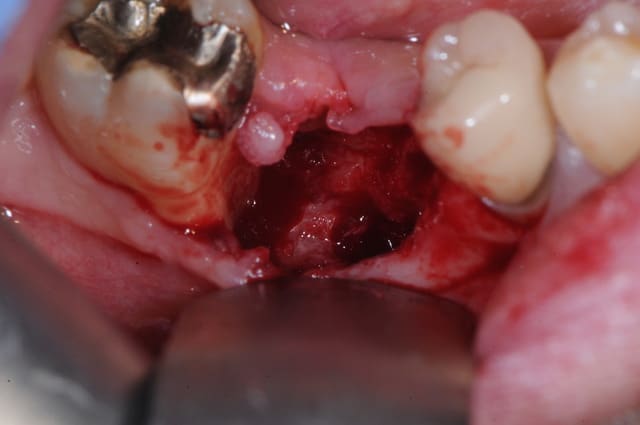

patient qui consulte lundi dernier pour avis implantaire pour 46

je regarde et je vois un petit morceau osseux bien vilain qui dépasse.

je lui ai programmé rapidement une intervention pour ce matin afin de cureter.

il a simplement fallu tirer un peu sur le séquestre

il y a eu comblement osseux avec biooss et mise en place de mucograft seal (peu visible sur la photo) même si c'était PRESQUE pas nécessaire (bretelle et ceinture)